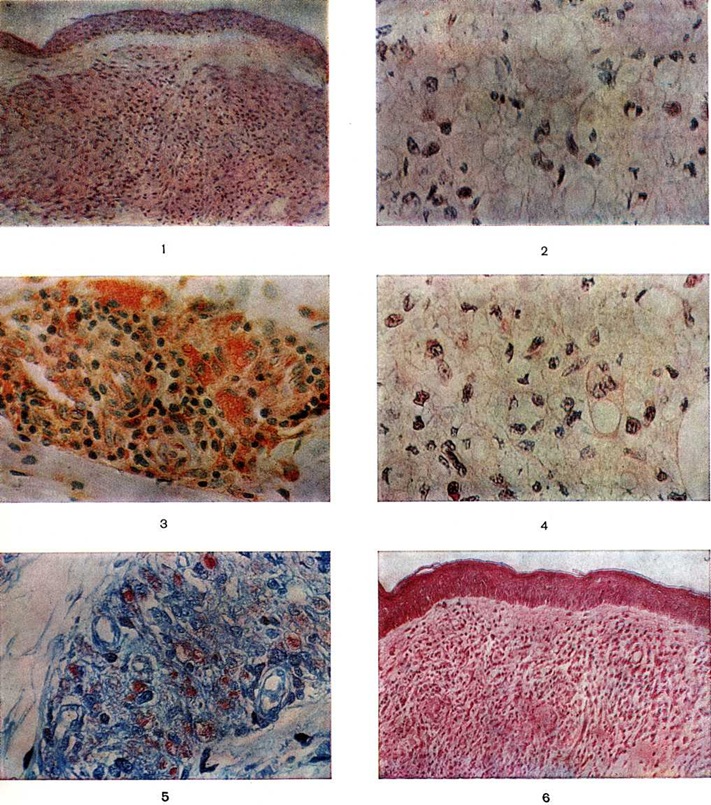

Гистологически лепроматозный тип характеризуется лепроматозной гранулемой кожи, которая представляет инфильтрат, расположенный в сетчатом слое, отделённый от эпидермиса непоражённой зоной коллагеновой ткани. Основными клеточными элементами лепроматозной гранулемы являются лепрозные клетки; кроме того, наблюдаются отдельные плазматические, лимфоидные клетки, единичные фибробласты, многоядерные пенистые клетки (цветной рисунок 1—6). Лепрозные клетки относятся к макрофагам, характеризуются бледным ядром и «пенистой» цитоплазмой (рисунок 5) за счёт содержания липидов. Лепрозный макрофаг на ранних стадиях содержит жирные кислоты, фосфолипиды, ненасыщенные липиды; на стадии развития процесса преобладают нейтральные жиры и кислотные липиды. Большинство исследователей считает, что основная масса липидов представляет собой продукт метаболизма и распада микобактерий Лепра. Наиболее характерная особенность лепрозного макрофага — нахождение и размножение в нем большого количества микобактерий Лепра, то есть явление незавершённого фагоцитоза (смотри полный свод знаний). В цитоплазме лепрозной клетки выявляется высокий уровень окислительно-восстановительных ферментов, кислой фосфатазы, неспецифической эстеразы и не обнаруживается активность липазы. Для гистологический картины LL характерно также наличие капилляров со значительным сужением их просвета за счёт пролиферации и набухания эндотелиальных клеток, содержащих большое количество микобактерий типа «глоби». Кожные нервы пронизаны инфильтратами из микробосодержащих клеток (цветной рисунок 7 и 10). Микобактерии обнаруживаются также в клетках эндоневрия. В лепроматозных поражениях большой давности отмечается частичное или полное разрушение придатков кожи (фолликулов волос, сальных и потовых желёз).

При гистоидной Лепра [атипичный вариант LL, описан Уэйдом (Н. W. Wade, 1963)] инфильтрат представлен множеством тонких веретенообразных клеток, образующих переплетающиеся тяжи и завитки. Количество микобактерий в этих клетках больше, чем при обычных лепроматозных поражениях; бактерии занимают почти всю их цитоплазму. Возможно сочетание гистоидной Лепра с элементами туберкулоидных структур или обычного лепроматозного инфильтрата.

При туберкулоидном типе патологический процесса сформировавшийся инфильтрат может быть массивным, занимающим все слои собственно кожи, или располагаться отдельными очагами. Характерно разрушение субэпидермального слоя коллагеновой ткани с расположением гранулемы непосредственно под эпидермисом с эрозированием последнего. Основную массу гранулемы составляют эпителиоидные клетки (смотри полный свод знаний), расположенные в центре и окружённые по периферии валом из лимфоидных клеток (смотри полный свод знаний Лимфоциты), встречаются гигантские многоядерные клетки типа Лангханса (смотри полный свод знаний Гигантские клетки), в небольшом количестве обнаруживаются плазматические клетки (смотри полный свод знаний), тучные клетки (смотри полный свод знаний), фибробласты. В период обострения в гранулеме наблюдается обилие полиморфно-ядерных лейкоцитов (смотри полный свод знаний). Клеточные элементы не содержат микобактерий и липидов. Характерно утолщение нервных стволов за счёт массивной инфильтрации эпителиоидными клетками.

Морфологически структуры, содержащие элементы, характерные для обоих типов Лепра и являющиеся как бы переходной стадией между полярными типами, характерны для пограничной Лепра При недифференцированной Лепра наблюдается картина банального хронический воспаления (смотри полный свод знаний) без специфических изменений. Основными гистологический критериями, определяющими принадлежность к классификационным группам Ридли — Джоплинга, являются следующие морфологический особенности инфильтрата. 1. Клеточный состав гранулемы. В верхней половине спектра (ТТ, ВТ и ВВ) характерно наличие эпителиоидных клеток (цветной рисунок 8) и для ТТ — многоядерных (гигантских) клеток типа Лангханса (цветной рисунок 9). При ВВ эпителиоидные клетки часто отделены друг от друга отёком. В нижней части спектра (BL и LL) эпителиоидные клетки уступают место макрофагам, цитоплазма которых по мере приближения к типу LL становится более плотной, пенистой и содержит жир. 2. Плотность популяций микобактерий. Количество микобактерий возрастает пропорционально от верхней части спектра к нижней. В числовом выражении показатель бактериальной насыщенности лепроматозного инфильтрата для ТТ, ВТ, ВВ, BL и LL составляет 0/1; 0/2,5; 3/4,5; 4/5,5; 5/6,5 соответственно. 3. Количество и топография лимфоцитов в гранулеме. Для ТТ и ВТ свойственно высокое содержание лимфоцитов, расположенных в виде плотного бордюра вокруг массы эпителиоидных клеток. При ВВ и LL количество лимфоцитов чаще снижено, они рассеяны по гранулеме и не образуют вала. 4. Поражение кожных нервов. Для туберкулоидной части спектра характерно значительное утолщение нерва за счёт массивного инфильтрата (повышение максимального диаметра пучка при ТТ). Для ВВ и BL патогномоничны изменения периневрия в виде луковичной кожуры (onion skin) за счёт расслоения его инфильтратом из лимфоцитов, плазмоцитов (при В В) или бактериосодержащих макрофагов (при BL). 5. Отношение к эпидермису. При ТТ и ВТ гранулема располагается непосредственно под эпидермисом и может эрозировать его. При ВВ, BL и LL между инфильтратом и эпидермисом постоянно остаётся непоражённая зона толщиной 30 — 75 микрометров — так называемый слой Ипа, состоящий из коллагеновой ткани.